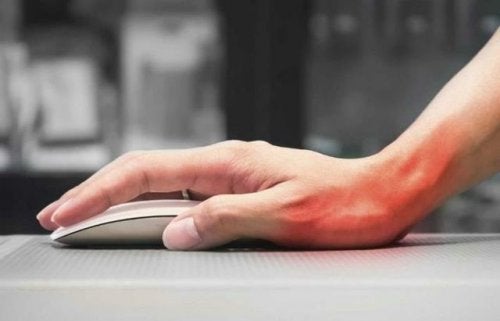

Las principales causas son movimientos repetitivos de pies o manos, así como también las malas posturas.

En los movimientos repetitivos hay excesiva fricción del tendón con el hueso y por ello hay desgaste y lesiones en la vaina que rodea los tendones para dar paso a la inflamación.

- Levantar en brazos a un niño, coser o escribir en el computador puede ocasionar tenosinovitis.